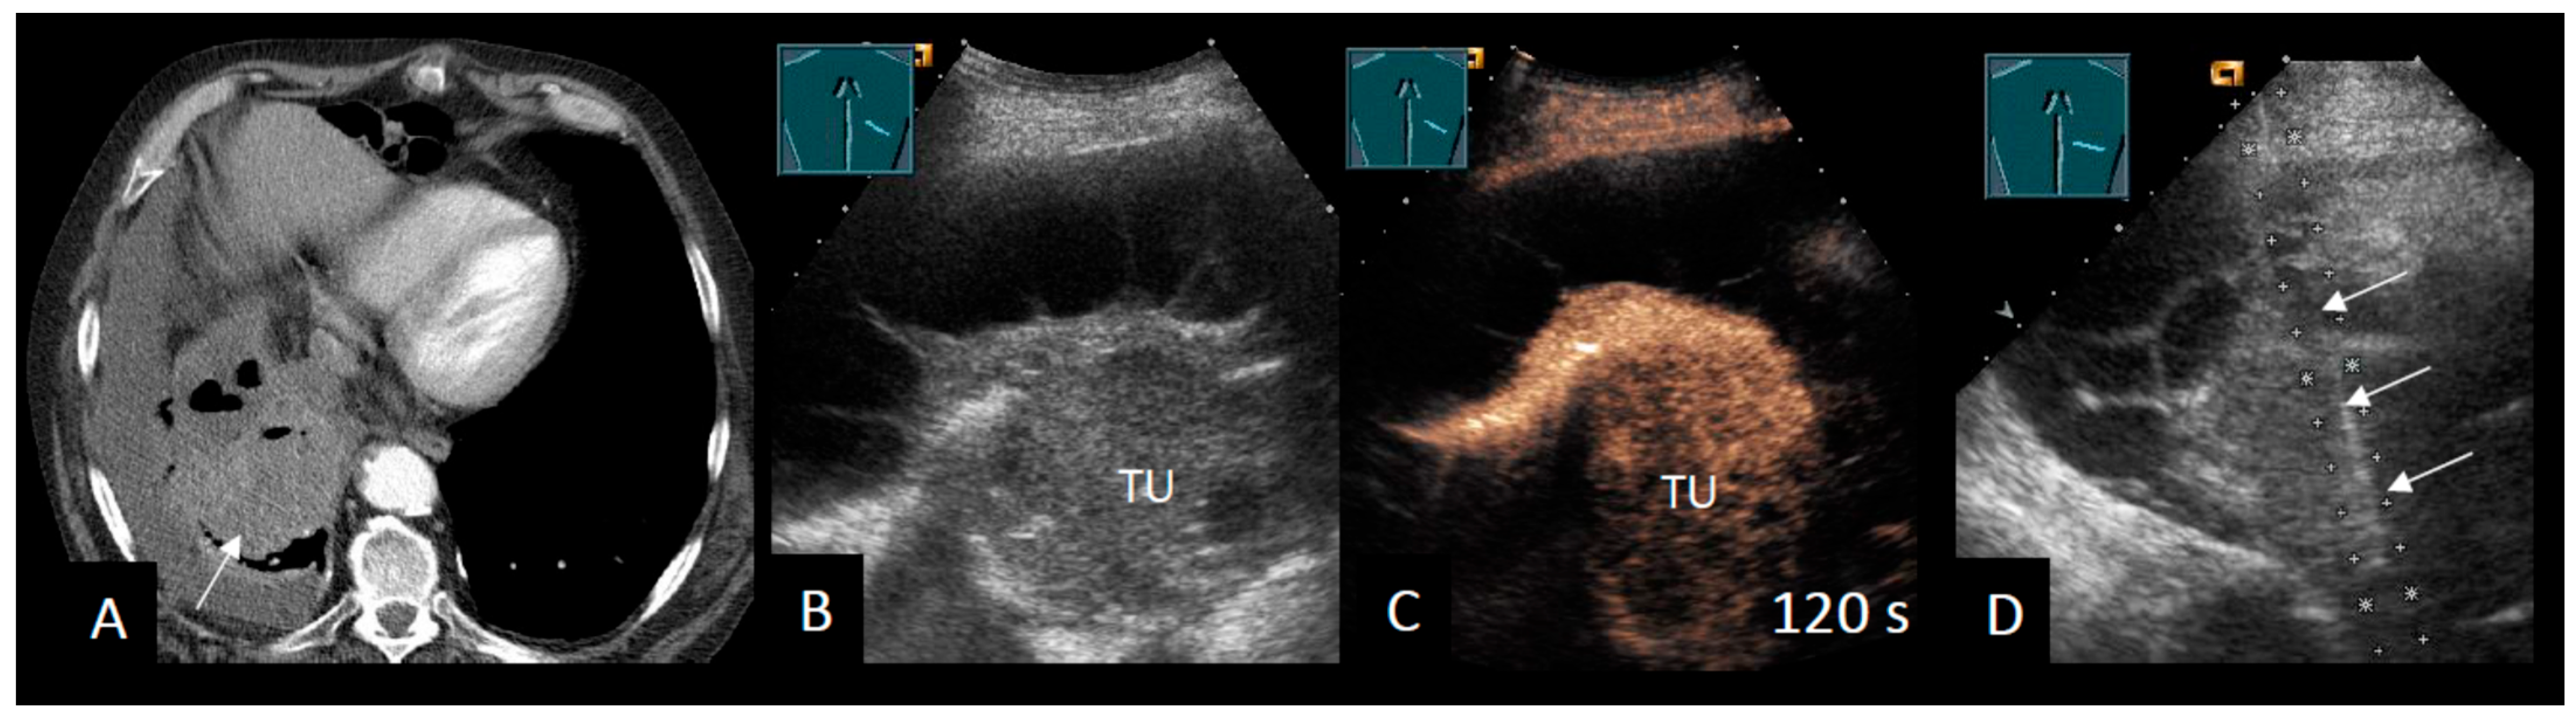

2.4. Intrapulmonary Lesions

Additional Ultrasound Techniques

| CEUS | ||||

| Safai Zadeh et al. [53] | 2021 | n = 83, single-center, retrospective study | To evaluate the value of CEUS in differentiating malignant from benign PE | Sensitivity B-mode: 69.1% Specificity B-mode: 58.5% Sensitivity CEUS: 73.8% Specificity CEUS: 70.7% Subgroup (cytological negative, high risk for MPE): Sensitivity CEUS: 92.3% Specificity CEUS: 90.0% |

| Findeisen et al. [56] | 2022 | n = 63, single-center, retrospective study | To describe the value of CEUS for the differentiation of malignant from benign parietal pleural lesions (Pleural effusion in 50.8%) | Sensitivity CEUS: 92% Specificity CEUS: 54% |

| Yang et al. [58] | 2022 | n = 50, single-center, prospective study | To investigate the diagnostic capabilities of B-mode LUS and CEUS in terms of differentiating between benign and malignant pleural diseases | Multivariate logistic regression: Sensitivity 93.3% Specificity 90.0% |